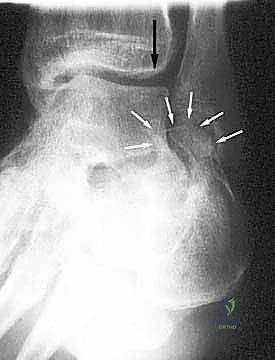

- الأشعة السينية (X-rays) متعددة الزوايا: لتقييم الانهيار العظمي وزوايا الكعب (مثل زاوية بوهلر وزاوية جيسان).

- الأشعة المقطعية ثلاثية الأبعاد (3D CT Scan): وهي الخطوة الذهبية والأهم في عيادة الدكتور هطيف. تتيح هذه الأشعة بناء نموذج ثلاثي الأبعاد دقيق للكعب المشوه، مما يسمح بتحديد أماكن الانحشار العظمي بدقة المليمتر، ومعرفة مدى تلف الأسطح المفصلية. بناءً على هذه الصور، يتم وضع خطة "القطع العظمي التصحيحي" قبل دخول غرفة العمليات.

- القطع العظمي التصحيحي (Corrective Osteotomy):

إذا كان الكعب قد فقد ارتفاعه أو انحرف بشكل كبير، يقوم الدكتور هطيف بإجراء قطع دقيق في عظم الكعب لإعادة توجيهه إلى محوره الميكانيكي السليم. يتم استخدام طعوم عظمية (Bone Grafts)—تؤخذ غالباً من حوض المريض أو طعوم صناعية—لرفع الكعب المنهار واستعادة زاوية بوهلر الطبيعية.